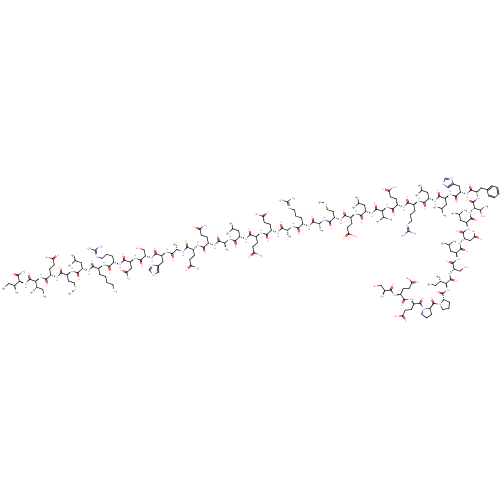

TargetCorticotropin-releasing factor receptor 1(Homo sapiens (Human))

Dupont Pharmaceuticals

Curated by ChEMBL

Dupont Pharmaceuticals

Curated by ChEMBL

Affinity DataEC50: 0.220nMAssay Description:Activity of peptidic agonists on corticotropin releasing factor receptor receptor using agonist-stimulated adenylate cyclase assayMore data for this Ligand-Target Pair